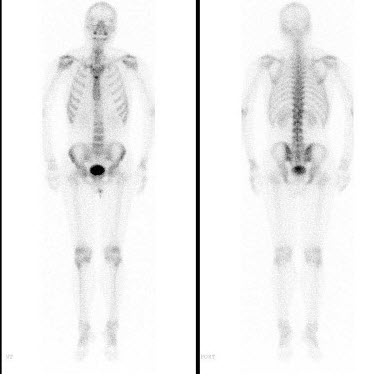

61、多项选择题

男,69岁,肺癌化疗中,诉下肢疼痛3个月,行全身骨显像如图,可能的诊断()

A.未见骨转移征象

B.双侧膝关节转移瘤

C.双侧胫骨转移瘤

D.双下肢肥大性骨关节病

E.有“热髌征”